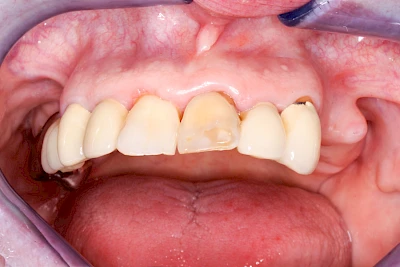

Heute werden in Deutschland Menschen mit Lippen-Kiefer-Gaumenspalten bereits ab Geburt von Experten verschiedener Fachrichtungen (Mund-Kiefer-Gesichtschirurgen, Kieferorthopäden, Logopäden) betreut, damit entsprechende Korrekturen schon frühzeitig erfolgen können. Gerade jedoch bei älteren Menschen ist dies nicht immer geschehen. Diese Menschen tragen häufig technisch aufwendige Zahnprothesen.